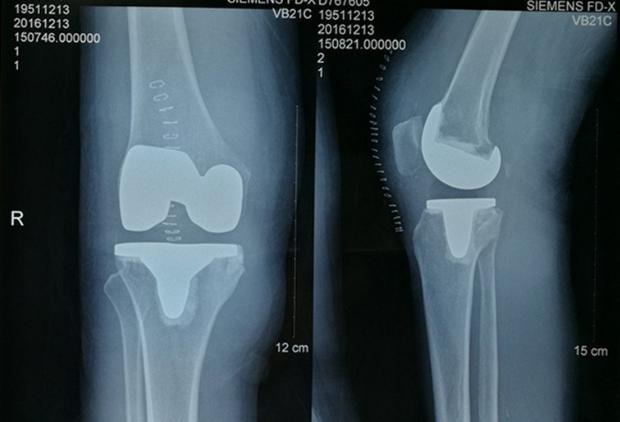

日常生活中用到膝关节的地方非常多,我们走的每一步都跟膝关节有关。因此膝关节的病变以及损伤所带来的痛苦能使人对生活感到心灰意冷,连正常的蹲下都做不到,行走也变得困难。受此影响大部分患者会选择全膝关节置换手术,能最大限度的帮助患者重返工作岗位,建立信心。关节置换不仅要有成功的关节置换手术,更重要的是对置换后的康复训练,怎么能更好的跟“新关节”相处对于关节置换术的效果具有重要意义。关节置换术后一定要注意康复训练。